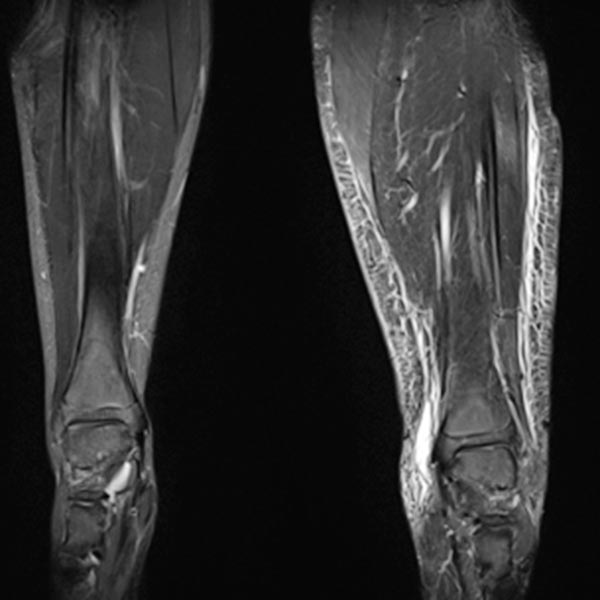

Coronal, T2-weighted, fat-suppressed MRI of both lower legs. Marked subcutaneous edema on the affected left side due to chronic venous hypertension.